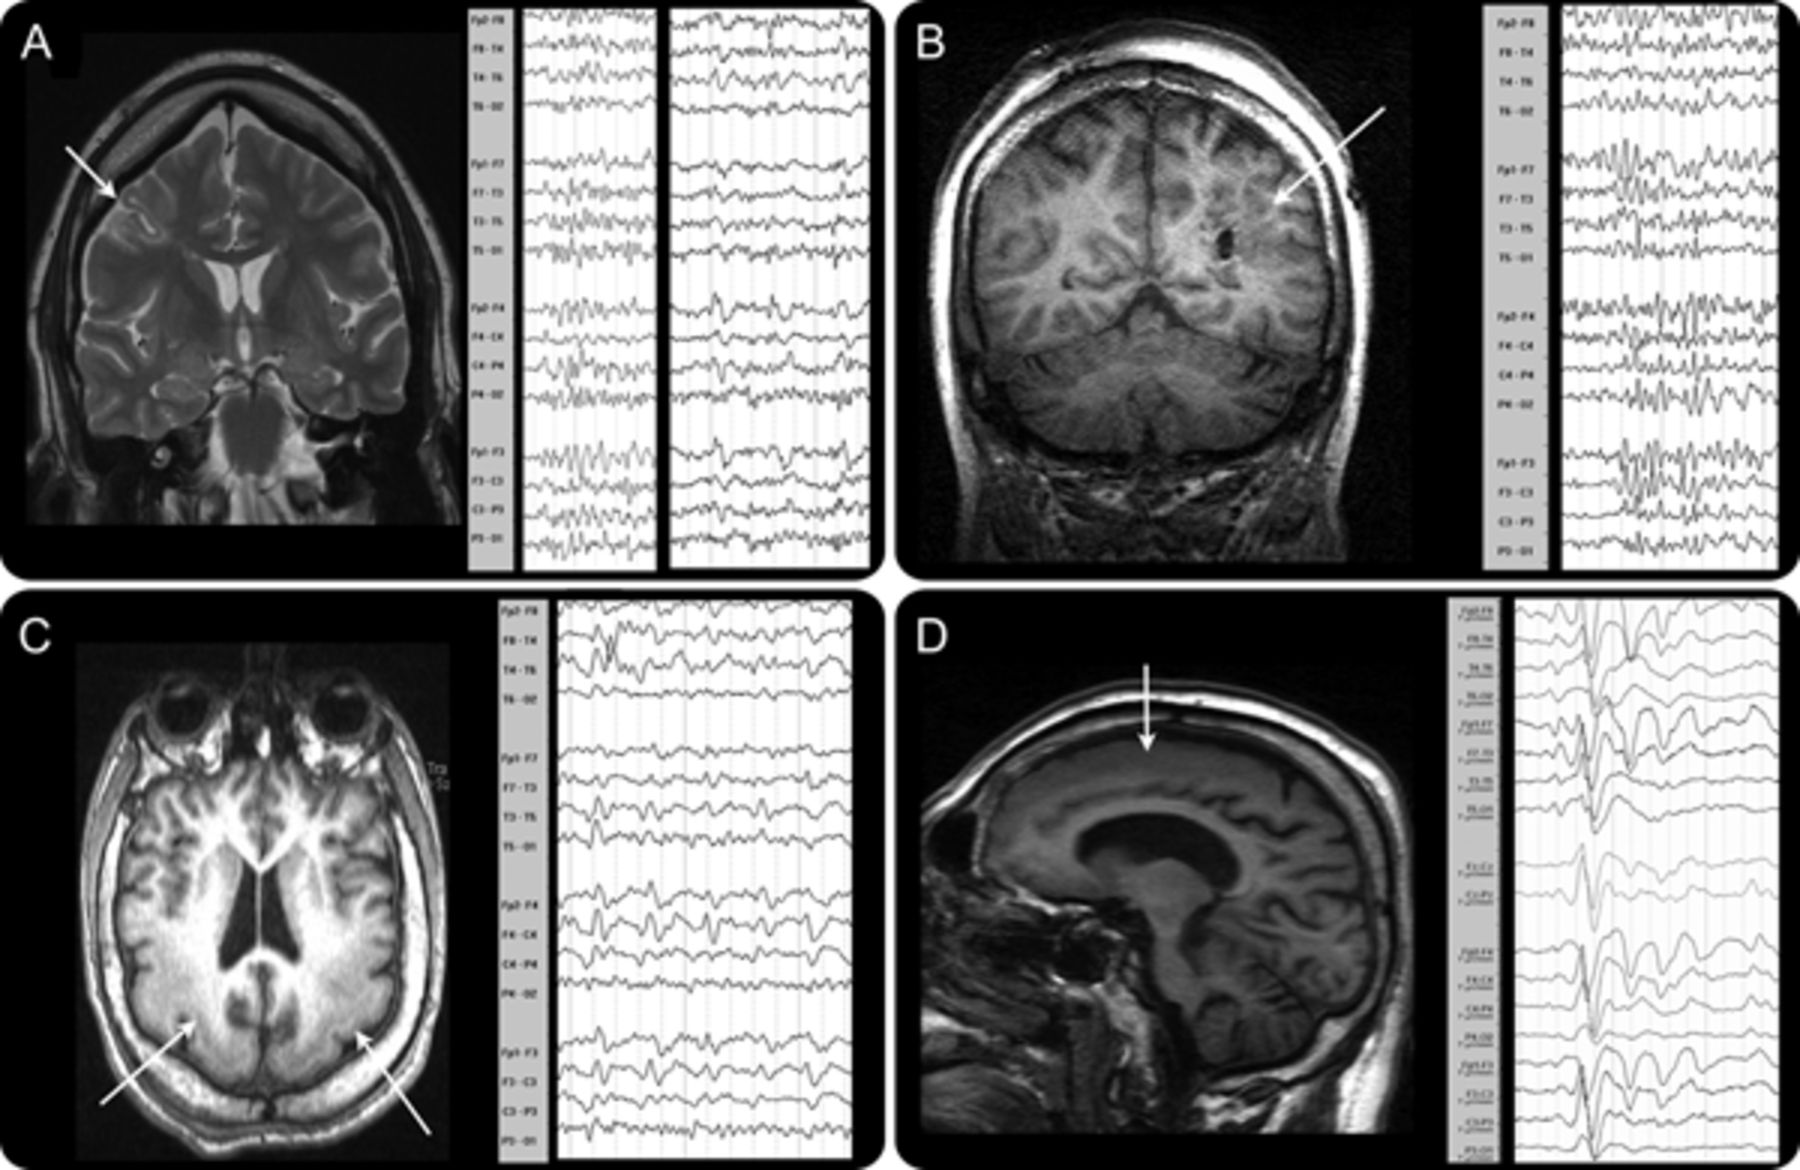

摘要目的:使用EEG-fMRI确定哪些结构极度参与阵发性快速活动的一代(PFA)和缓慢的上升和波(f)(1.5 - -2.5赫兹)的特征发作放电Lennox-Gastaut综合症(LGS)。